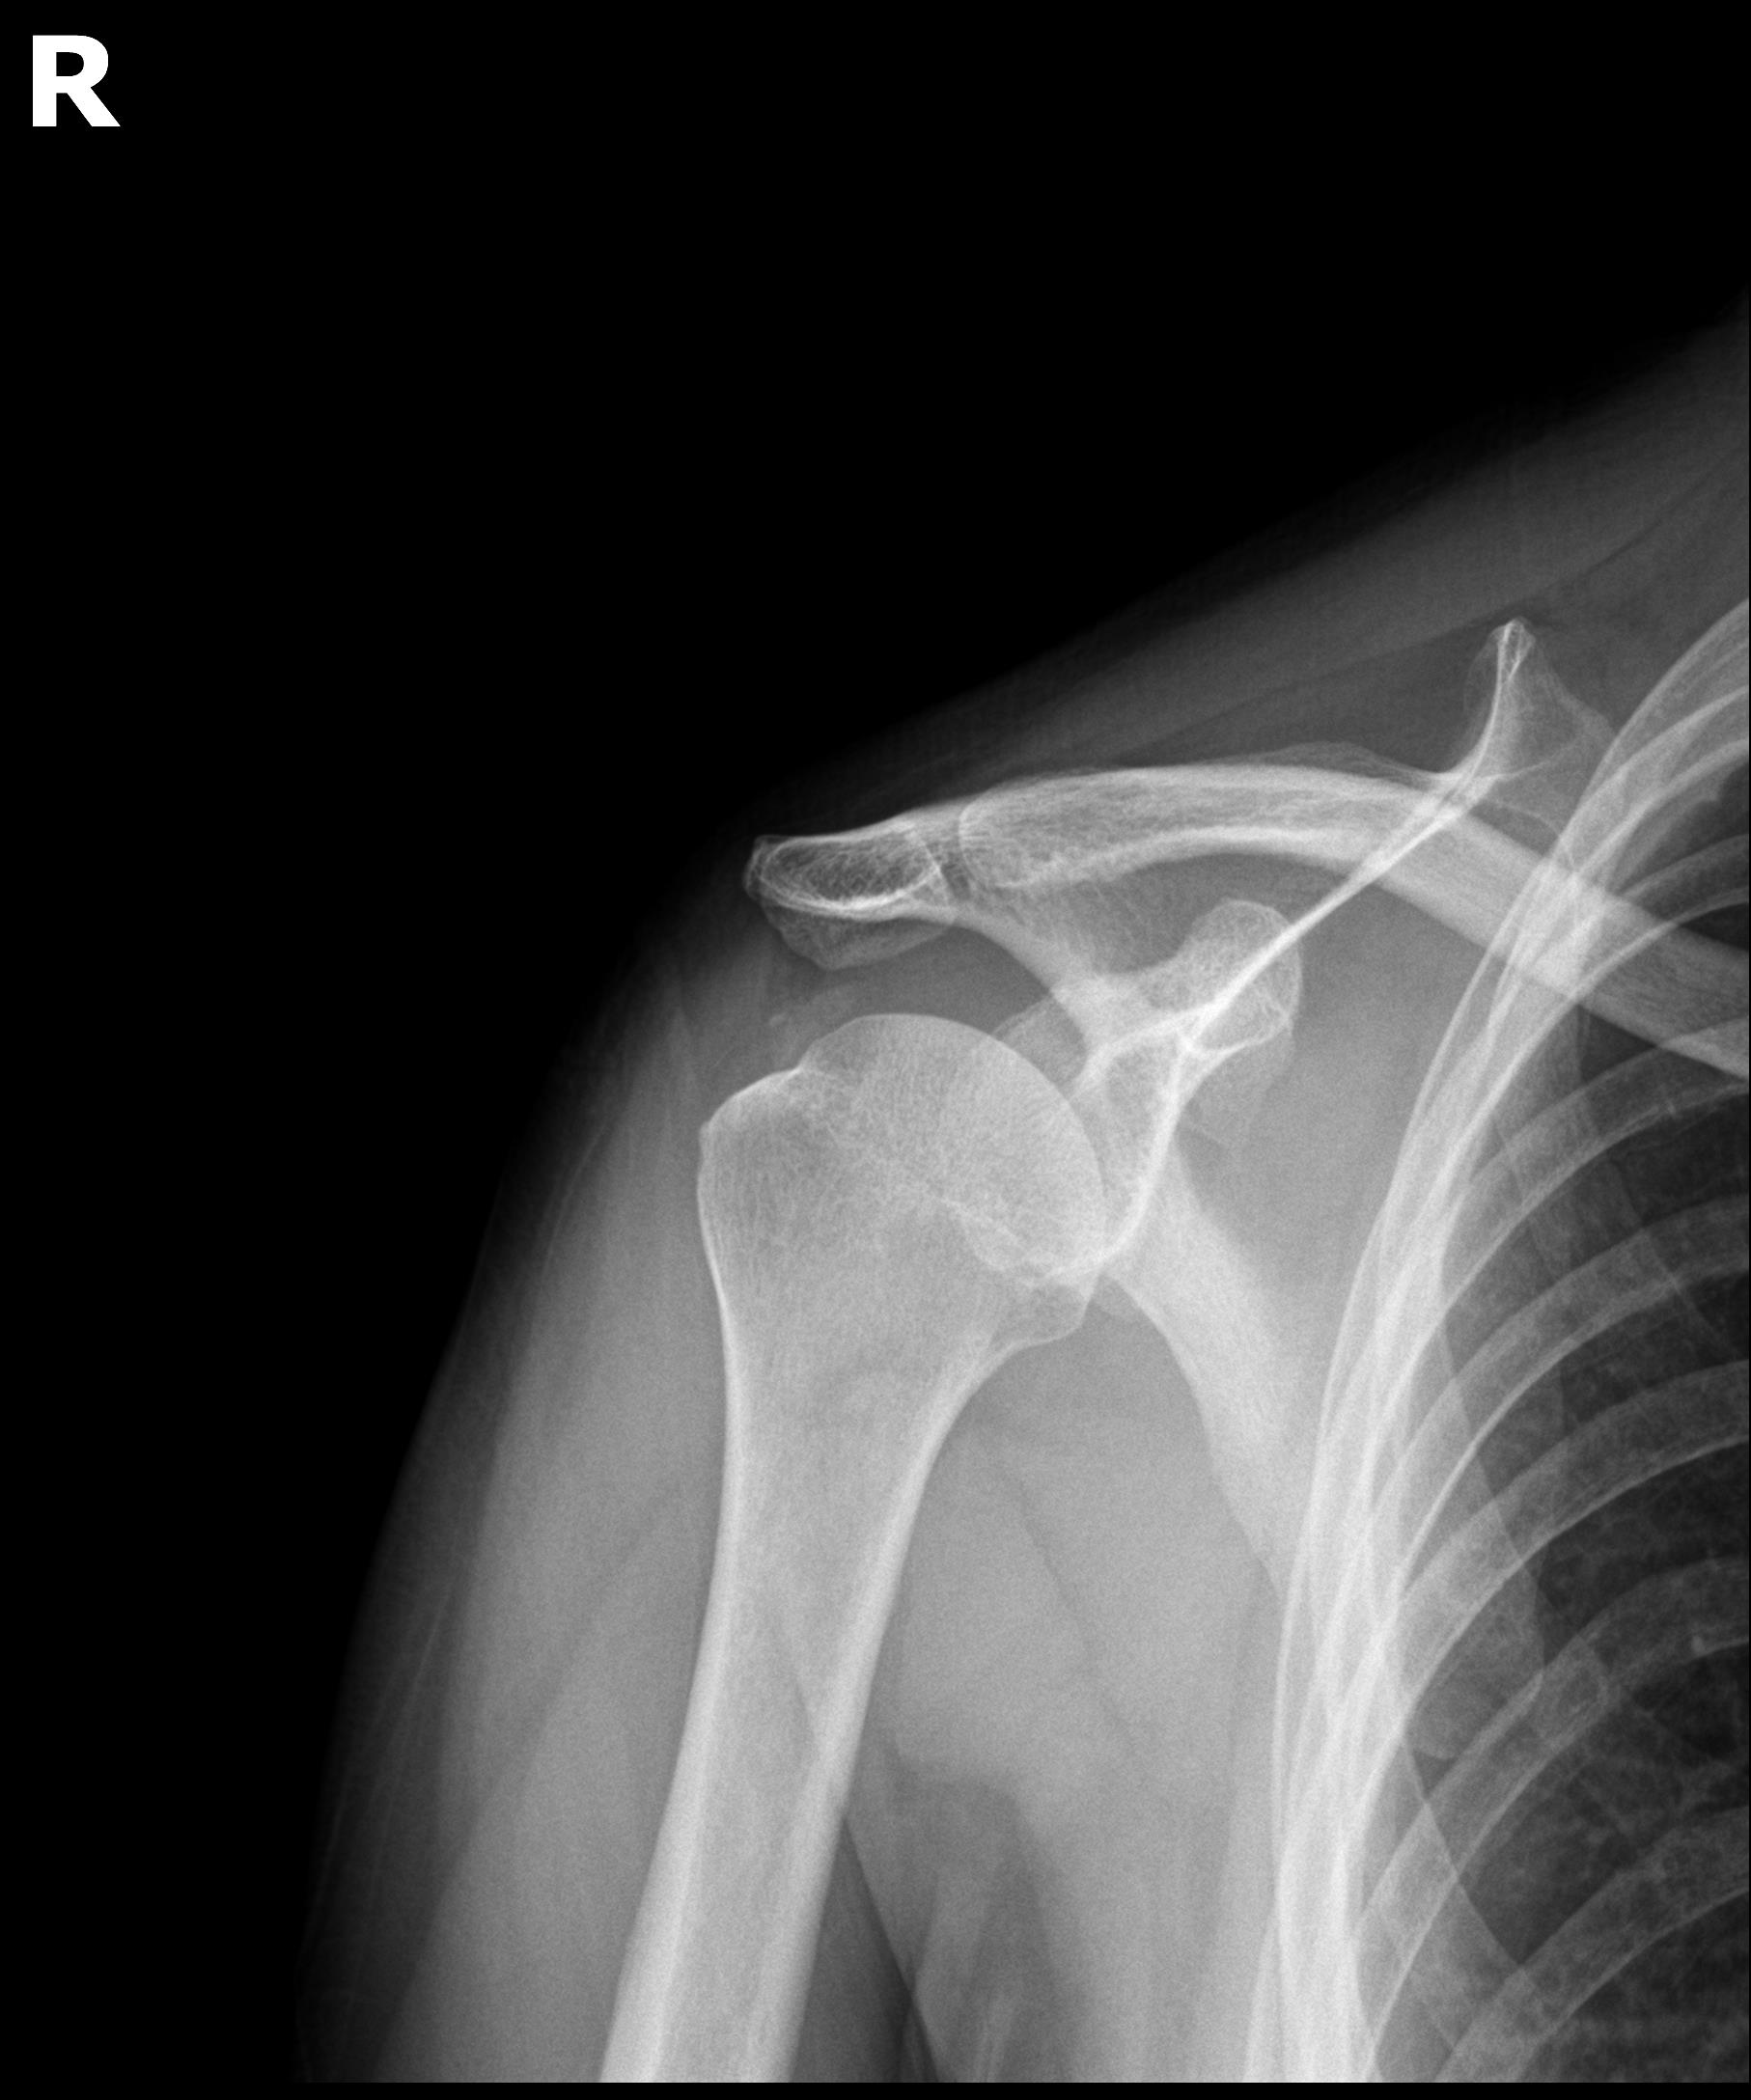

케이스 1: 형성기 단단한 석회 (1회 제거)

환자: 50대 남성, 우측 어깨 통증 8개월

시술 전:

X-ray에서 약 1.5cm 크기의 석회 확인

형성기 석회 (매우 단단)

타 병원에서 "수술 권유" 받음

시술 후:

1회 분쇄흡입술로 완전 제거

시술 직후 X-ray에서 석회 없음 확인

플래티넘에서의 치료

진단:

X-ray: 약 1.3cm 석회 (휴지기)

초음파: 석회 주변 인대 염증 소견

시술:

상완신경총 차단 마취

석회분쇄흡입술 시행

시술 시간: 35분

결과:

시술 직후 X-ray에서 석회 완전 제거 확인

기존 인대 염증은 재생주사로 추가 치료